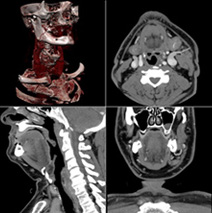

Åö±¡¤Ç¤Ï¡¢Àè¿ÊŪ¤ÊCTÁõÃ֤Ǥ¢¤ë320ÎóCT¤È2´ÉµåCT¤Î2Âæ¤òƳÆþ¤·¤Æ¤¤¤Þ¤¹¡£ ¤³¤ì¤é¤Ï

MDCT¡Ê¥Þ¥ë¥Á¥Ç¥£¥Æ¥¯¥¿¡¼CT¡Ë¤È¸Æ¤Ð¤ì¤ë¹âÀǽ¤ÊÁõÃ֤ǡ¢Ã»»þ´Ö¤Ç¿¤¯¤Î²èÁü¾ðÊó¤ò¼ý½¸¤Ç¤¤ë¤¿¤á¡¢¸¡ºº»þ´Ö¤Îû½Ì¤ä¡¢°ìÅ٤Ω»ß¤á¤Ç¹ÈϰϤλ£±Æ¤¬²Äǽ¤Ç¤¹¡£ÆÃ¤Ë2´ÉµåCT¤Ï¡¢Æ°¤¤Î®¤¤¿´Â¡¤Î»£±Æ¤Ë¤ª¤¤¤ÆÍ¥¤ì¤¿Àǽ¤òȯ´ø¤·¤Þ¤¹¡£½¾ÍèÁõÃÖ¤è¤ê¤â»þ´Öʬ²òǽ¤¬ÈôÌöŪ¤Ë¸þ¾å¤·¤¿¤³¤È¤Ç¡¢¿´Â¡¤Î·ÁÂ֤䴧ư̮¡Ê¿´Â¡¤òÍܤ¦·ì´É¡Ë¤ò¤è¤êÁ¯ÌÀ¤ËÉÁ¤½Ð¤·¡¢ÀºÅ٤ι⤤¿ÇÃǤ˹׸¥¤·¤Þ¤¹¡£

¤Þ¤¿¡¢CT-AEC¡ÊCT¼«Æ°Ïª½Ðµ¡¹½¡Ë¤äIR¡ÊÃ༡¶á»÷±þÍѺƹ½À®Ë¡¡Ë¤È¤¤¤Ã¤¿ºÇ¿·¤ÎÈï¤Ð¤¯Ä㸺µ»½Ñ¤òÀѶËŪ¤Ë³èÍѤ·¡¢¹â²è¼Á¤ò°Ý»ý¤·¤Ê¤¬¤é¡¢´µ¼Ô¤µ¤Þ¤ÎÈï¤Ð¤¯ÀþÎ̤ò²Äǽ¤Ê¸Â¤êÄ㸺¤¹¤ë¤è¤¦ÅØ¤á¤Æ¤¤¤Þ¤¹¡£